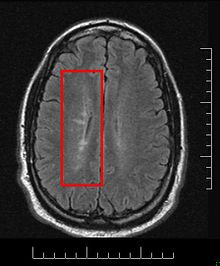

Dawson's Fingers appearing on an MRI scan

This morphologic appearance was named Dawson's fingers by Charles Lumsden, after the Scottish pathologist James Walker Dawson,[31] who first defined the condition in 1916.

Dawson's fingers[edit | edit source]

Image shows multiple lesions in periventricular and subcortical white matter, Dawson's finger is a characteristic finding in multiple sclerosis

"Dawson's fingers" is the name for the lesions around the ventricle-based brain veins[32][33] of patients with multiple sclerosis and antiMOG associated encephalomyelitis[34]

Though once thought to be specific of MS, it is known not to be the case.[35]

The condition is thought to be the result of inflammation or mechanical damage by blood pressure[30] around long axis of medular veins.

Dawson's fingers spread along, and from, large periventricular collecting veins, and are attributed to perivenular inflammation.[36]

Lesions far away from these veins are known as Steiner's splashes.[30]